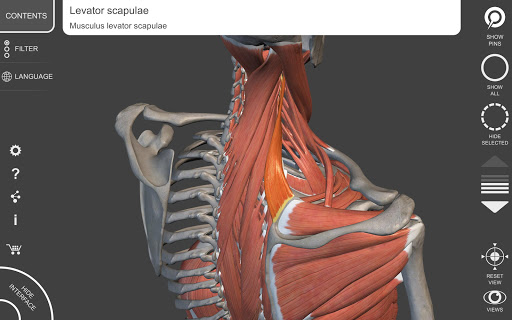

"Anatomy 3D Atlas" vous permet d'étudier l'anatomie humaine de manière simple et interactive.

Grâce à une interface simple et intuitive, il est possible d'observer chaque structure anatomique sous n'importe quel angle.

Les modèles anatomiques 3D sont particulièrement détaillés et avec des textures jusqu'à une résolution de 4k.

La subdivision par régions et les vues prédéfinies facilitent l'observation et l'étude de parties individuelles ou de groupes de systèmes et les relations entre différents organes.

• Visualisation des muscles à travers des niveaux de couches depuis les plus superficielles jusqu'aux plus profondes

• En sélectionnant un modèle ou une épingle, le terme anatomique associé apparaît

• Description des muscles : origine, insertion, innervation et action